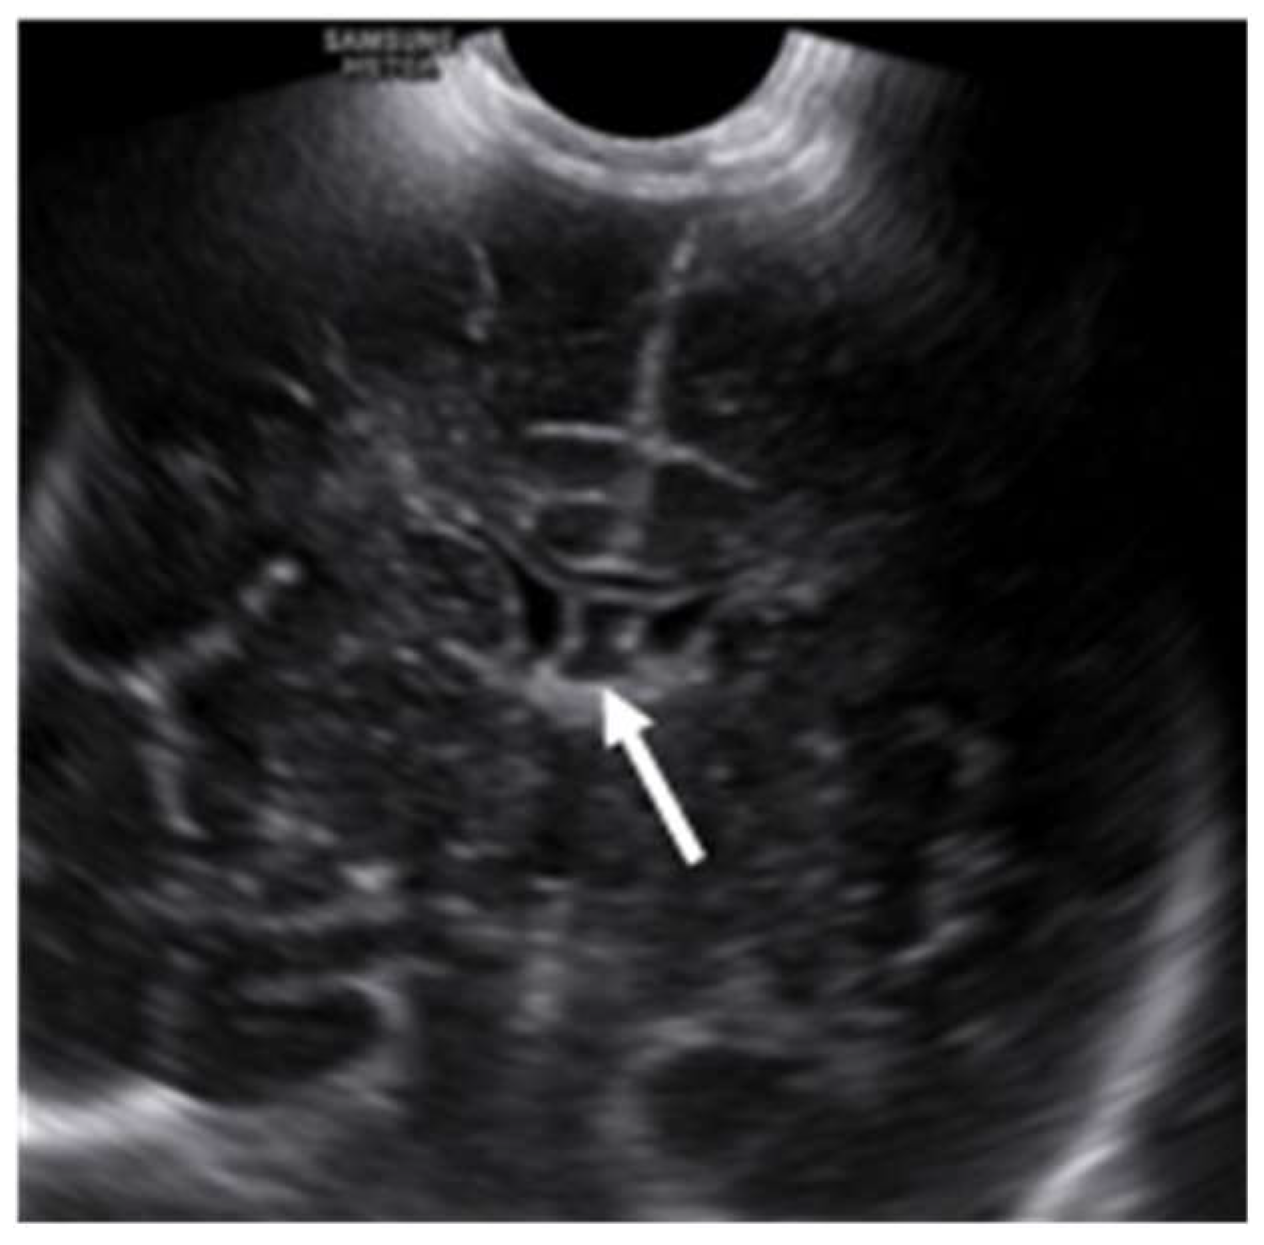

Ultrasonic evaluation of the brain

Ultrasonography (USG) is an extremely useful tool in the evaluation of foetal and infants’ brain during the latter two-thirds of the pregnancy to the first year of post-natal life. It is a cost-effective, non-invasive, easily accessible bedside test with a real-time imaging facility and a lack of ionizing radiation. In the post-natal period, SP and its variations are evaluated with axial and sagittal images through the anterior fontanelle with a symmetrical calvarium. Ultrasonically, the SP appears as a midline hyperechoic line inferior to the corpus callosum, separating the anterior horns of the lateral ventricles. The CSP appears as a fluid-filled box between the paired septa, which separates the CSP from the frontal horns of the lateral ventricles (Figure 6).

Winter et al. described the normal CSP on sonographic imaging as a fluid-filled low echogenic box between the echogenic paired septa, which separates the CSP from the frontal horns of the lateral ventricles (14). Jou et al. have shown that the width of CSP ranged from 2.0 mm to 10.0 mm with a mean width of 5.50 ± 1.48 mm after studying about 608 consecutive fetuses between 19 and 42 weeks of age (15).

Figure 6. Ultrasound scan of the brain of a day one neonate brain shows CSP (arrow) between lateral ventricles.